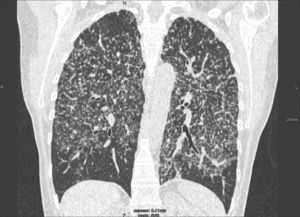

Patrón en «vidrio deslustrado»En la TCAR, el patrón en «vidrio deslustrado» se define como un tenue aumento de la densidad pulmonar de distribución a menudo geográfica, que no borra las estructuras vasculares adyacentes (fig. 4). Es un patrón inespecífico que se asocia a enfermedades alveolares, intersticiales o mixtas. En la enfermedad intersticial es visible cuando existe engrosamiento de los septos interlobulares o un grado mínimo de fibrosis. En la mayoría de los casos indica una patología potencialmente tratable. Se denomina patrón en «empedrado» (crazy-paving) a la superposición de un patrón lineal sobre un patrón en «vidrio deslustrado». Originalmente este patrón se describió asociado a la proteinosis alveolar, pero también se ha observado en la neumonía lipoidea exógena, en la hemorragia alveolar, en el daño alveolar difuso y en la infección por Pneumocystis jiroveci.

Imagen TCAR localizada en lóbulos inferiores que muestra un tenue aumento de densidad difuso, correspondiente a patrón en «vidrio deslustrado». Nótese que algunos lobulillos pulmonares no están afectados (flechas). Existe engrosamiento de las paredes bronquiales (cabeza de flecha) y una discreta dilatación esofágica (flecha negra).